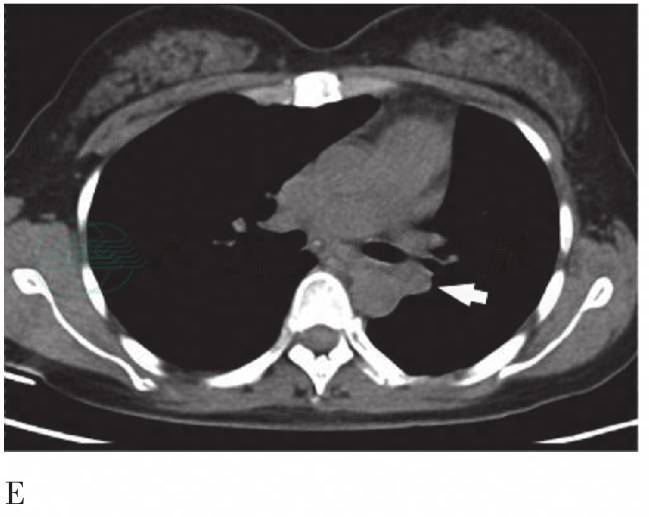

图2 2009年6月3日FDG PET/CT图像

A. PET MIP显像,颈部横断层图;B. CT纵隔窗;C. PET图像;D. PET/CT融合图像,胸部横断层图;E. CT纵隔窗;F. PET图像;G. PET/CT融合图像。右锁骨上多个淋巴结,边缘可见多发钙化,放射性摄取增高,SUVmax为4.1,延迟显像为5.2(长粗箭头);左锁骨上淋巴结放射性摄取增高,SUVmax为5.0,延迟显像为6.7(长细箭头)。CT示右上肺条索影伴多发钙化灶,双肺门及纵隔内多发钙化灶。左上纵隔可见3个淋巴结影放射性摄取异常增高,SUVmax为5.1、9.4,延迟显像为8.1、12.3;左肺术后改变,左肺门与降主动脉动脉间软组织影放射性摄取异常增高,SUVmax为7.5,延迟显像为10.7(短细箭头)